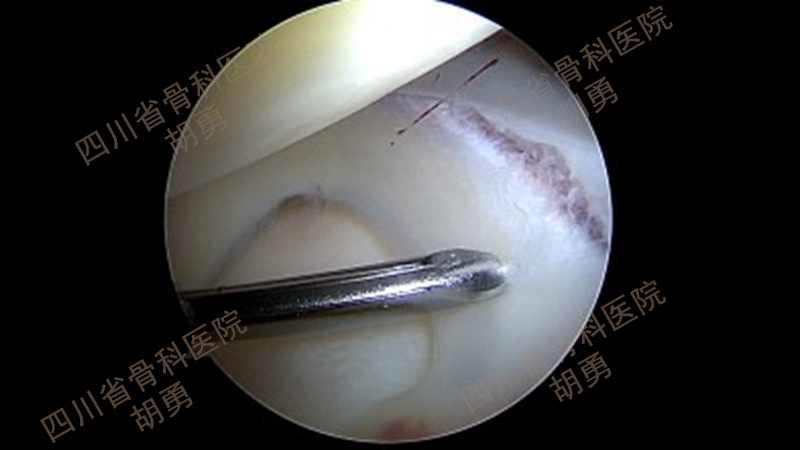

经前下外及前下内入口完成镜下检视,同期处理合并损伤。在本组病例中,常见的合并损伤主要是内、外侧半月板体部或(和)后角撕裂。对半月板后角常见的红-红或红-白区纵裂,可以通过镜下全内技术缝合挽救,如图3、4、5、6、7所示。

图5 镜下全内缝合撕裂半月板

图6 缝合后镜下所见